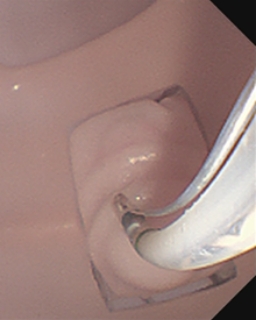

胆管挿管

EST